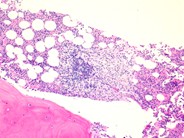

Scattered mast cells (arrows) with variable granulation are shown in this bone marrow aspirate.